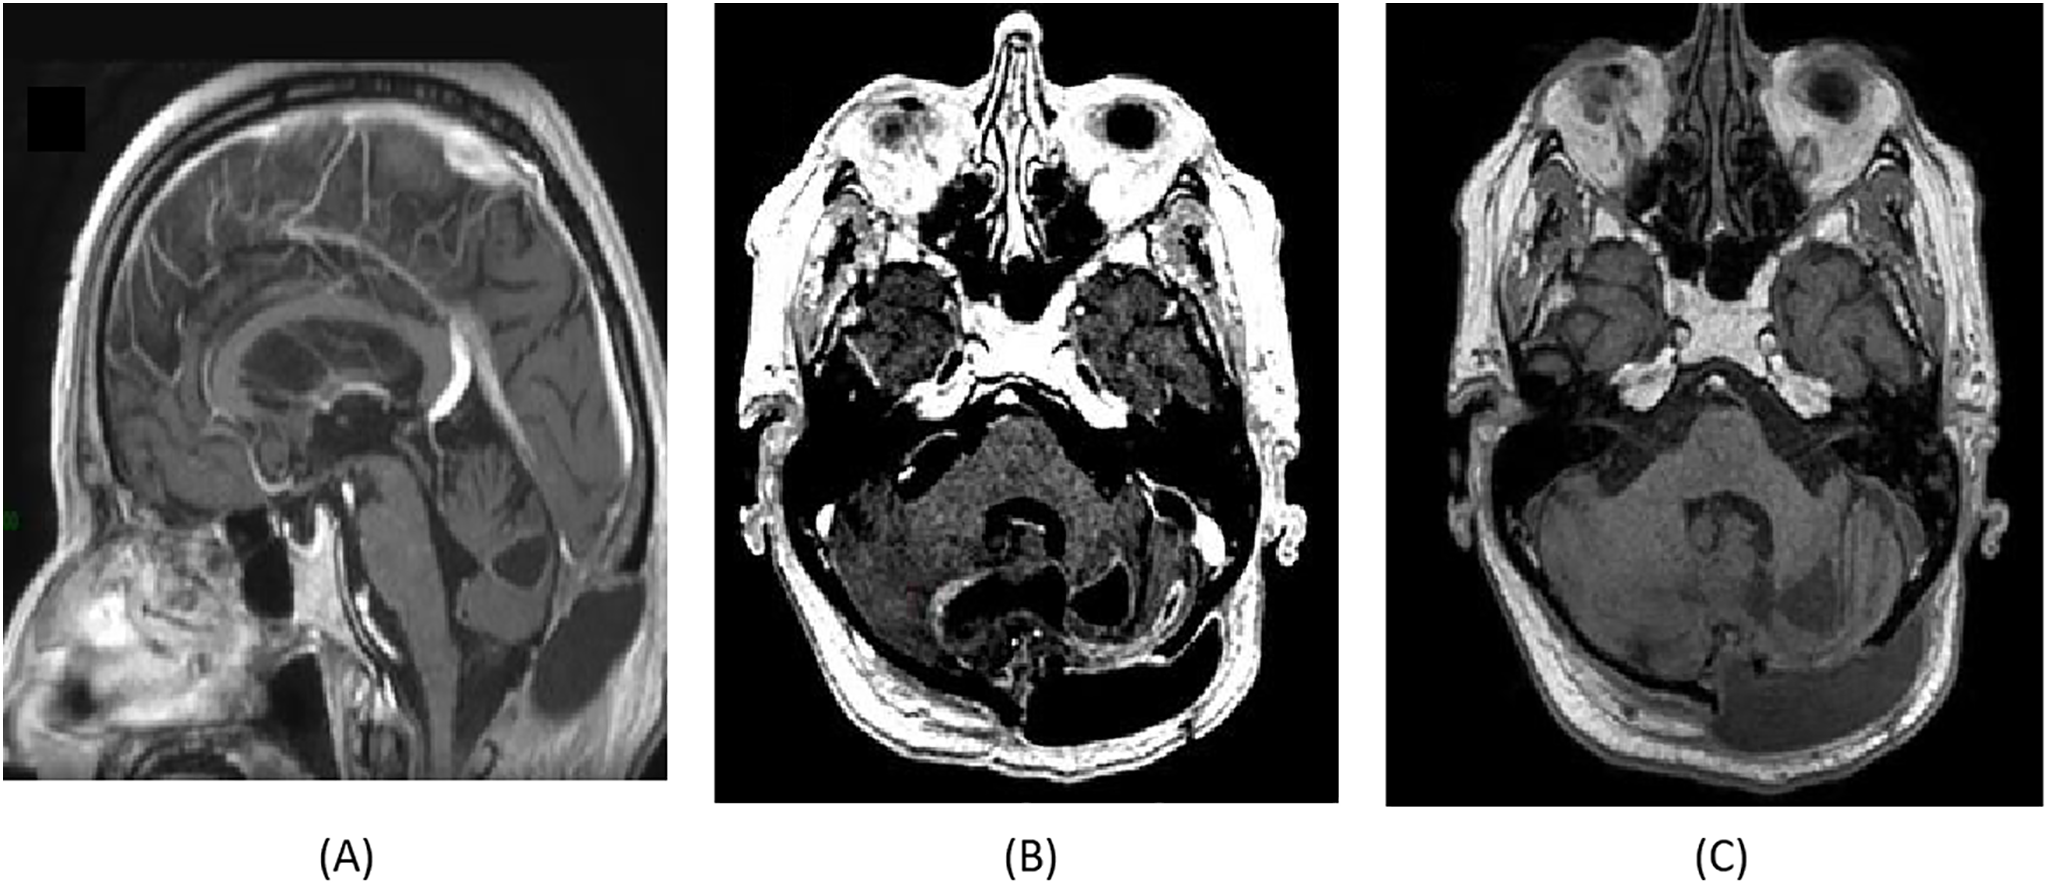

In the follow-up setting, brain MRI revealed a slight increase in the size of the fluid image of the left cerebellar surgical site exceeding the midline, with peripheral millimetric enhancement and hyperperfusion suspicious of recurrence (Fig. 4).

Fig. 4. (A) MRI Sagittal slice shows a slight increase in the size of the fluid-filled cavity, crossing the midline, with peripheral millimetric contrast enhancement and areas of hyperperfusion suggestive of tumor recurrence. (B) MRI Axial T1 with injection slices confirms the enlargement of the lesion with similar peripheral enhancement, reinforcing suspicion of recurrence. (C) Axial T1-weighted MRI slices without contrast show a hypointense fluid-filled lesion at the left cerebellar surgical site.